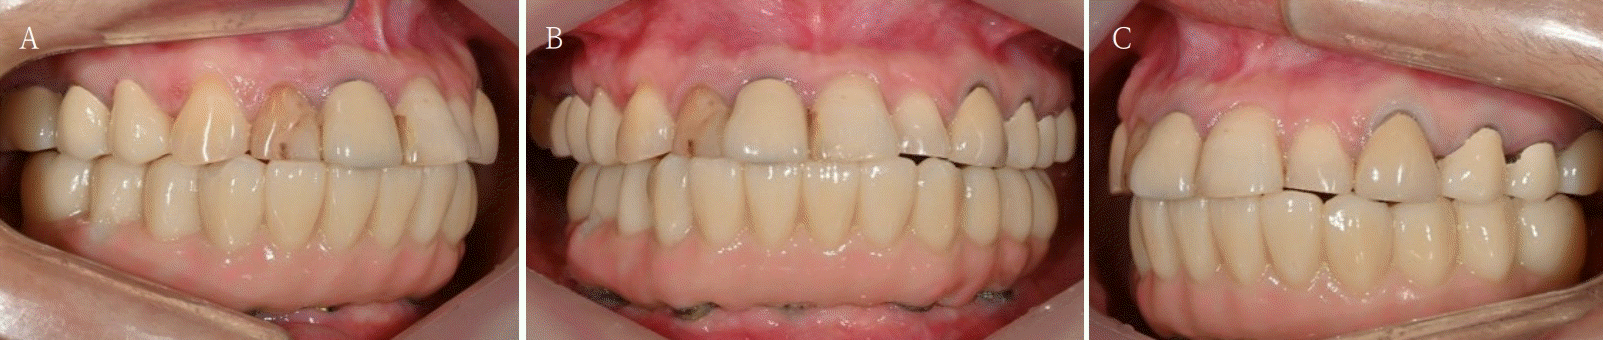

Fig. 5.

The patient is satisfied with the occlusion and vertical dimension of newly fabricated temporary denture. A. Right side view. B. Frontal view. C. Left side view.